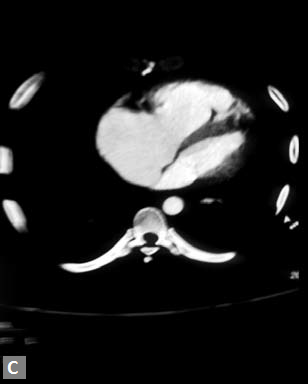

Right ventricular strain is picked up when RV/LV ratio is

more than one with deviation of interventricular septum to

left.